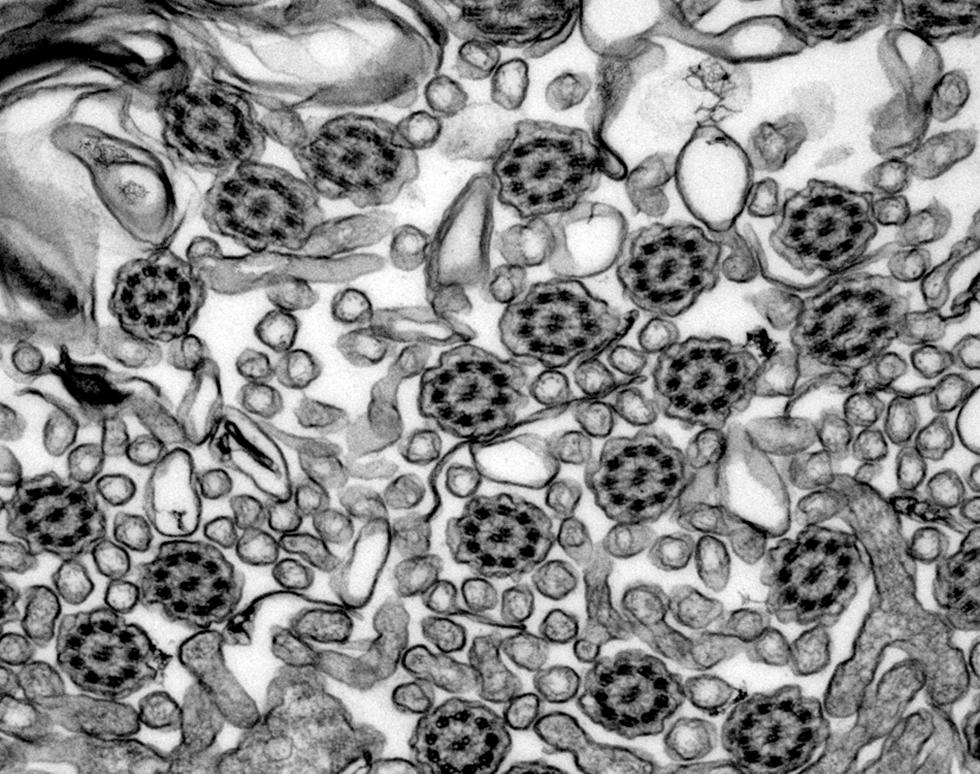

Cilia from patient with Primary Ciliary Diskynesia (PCD)